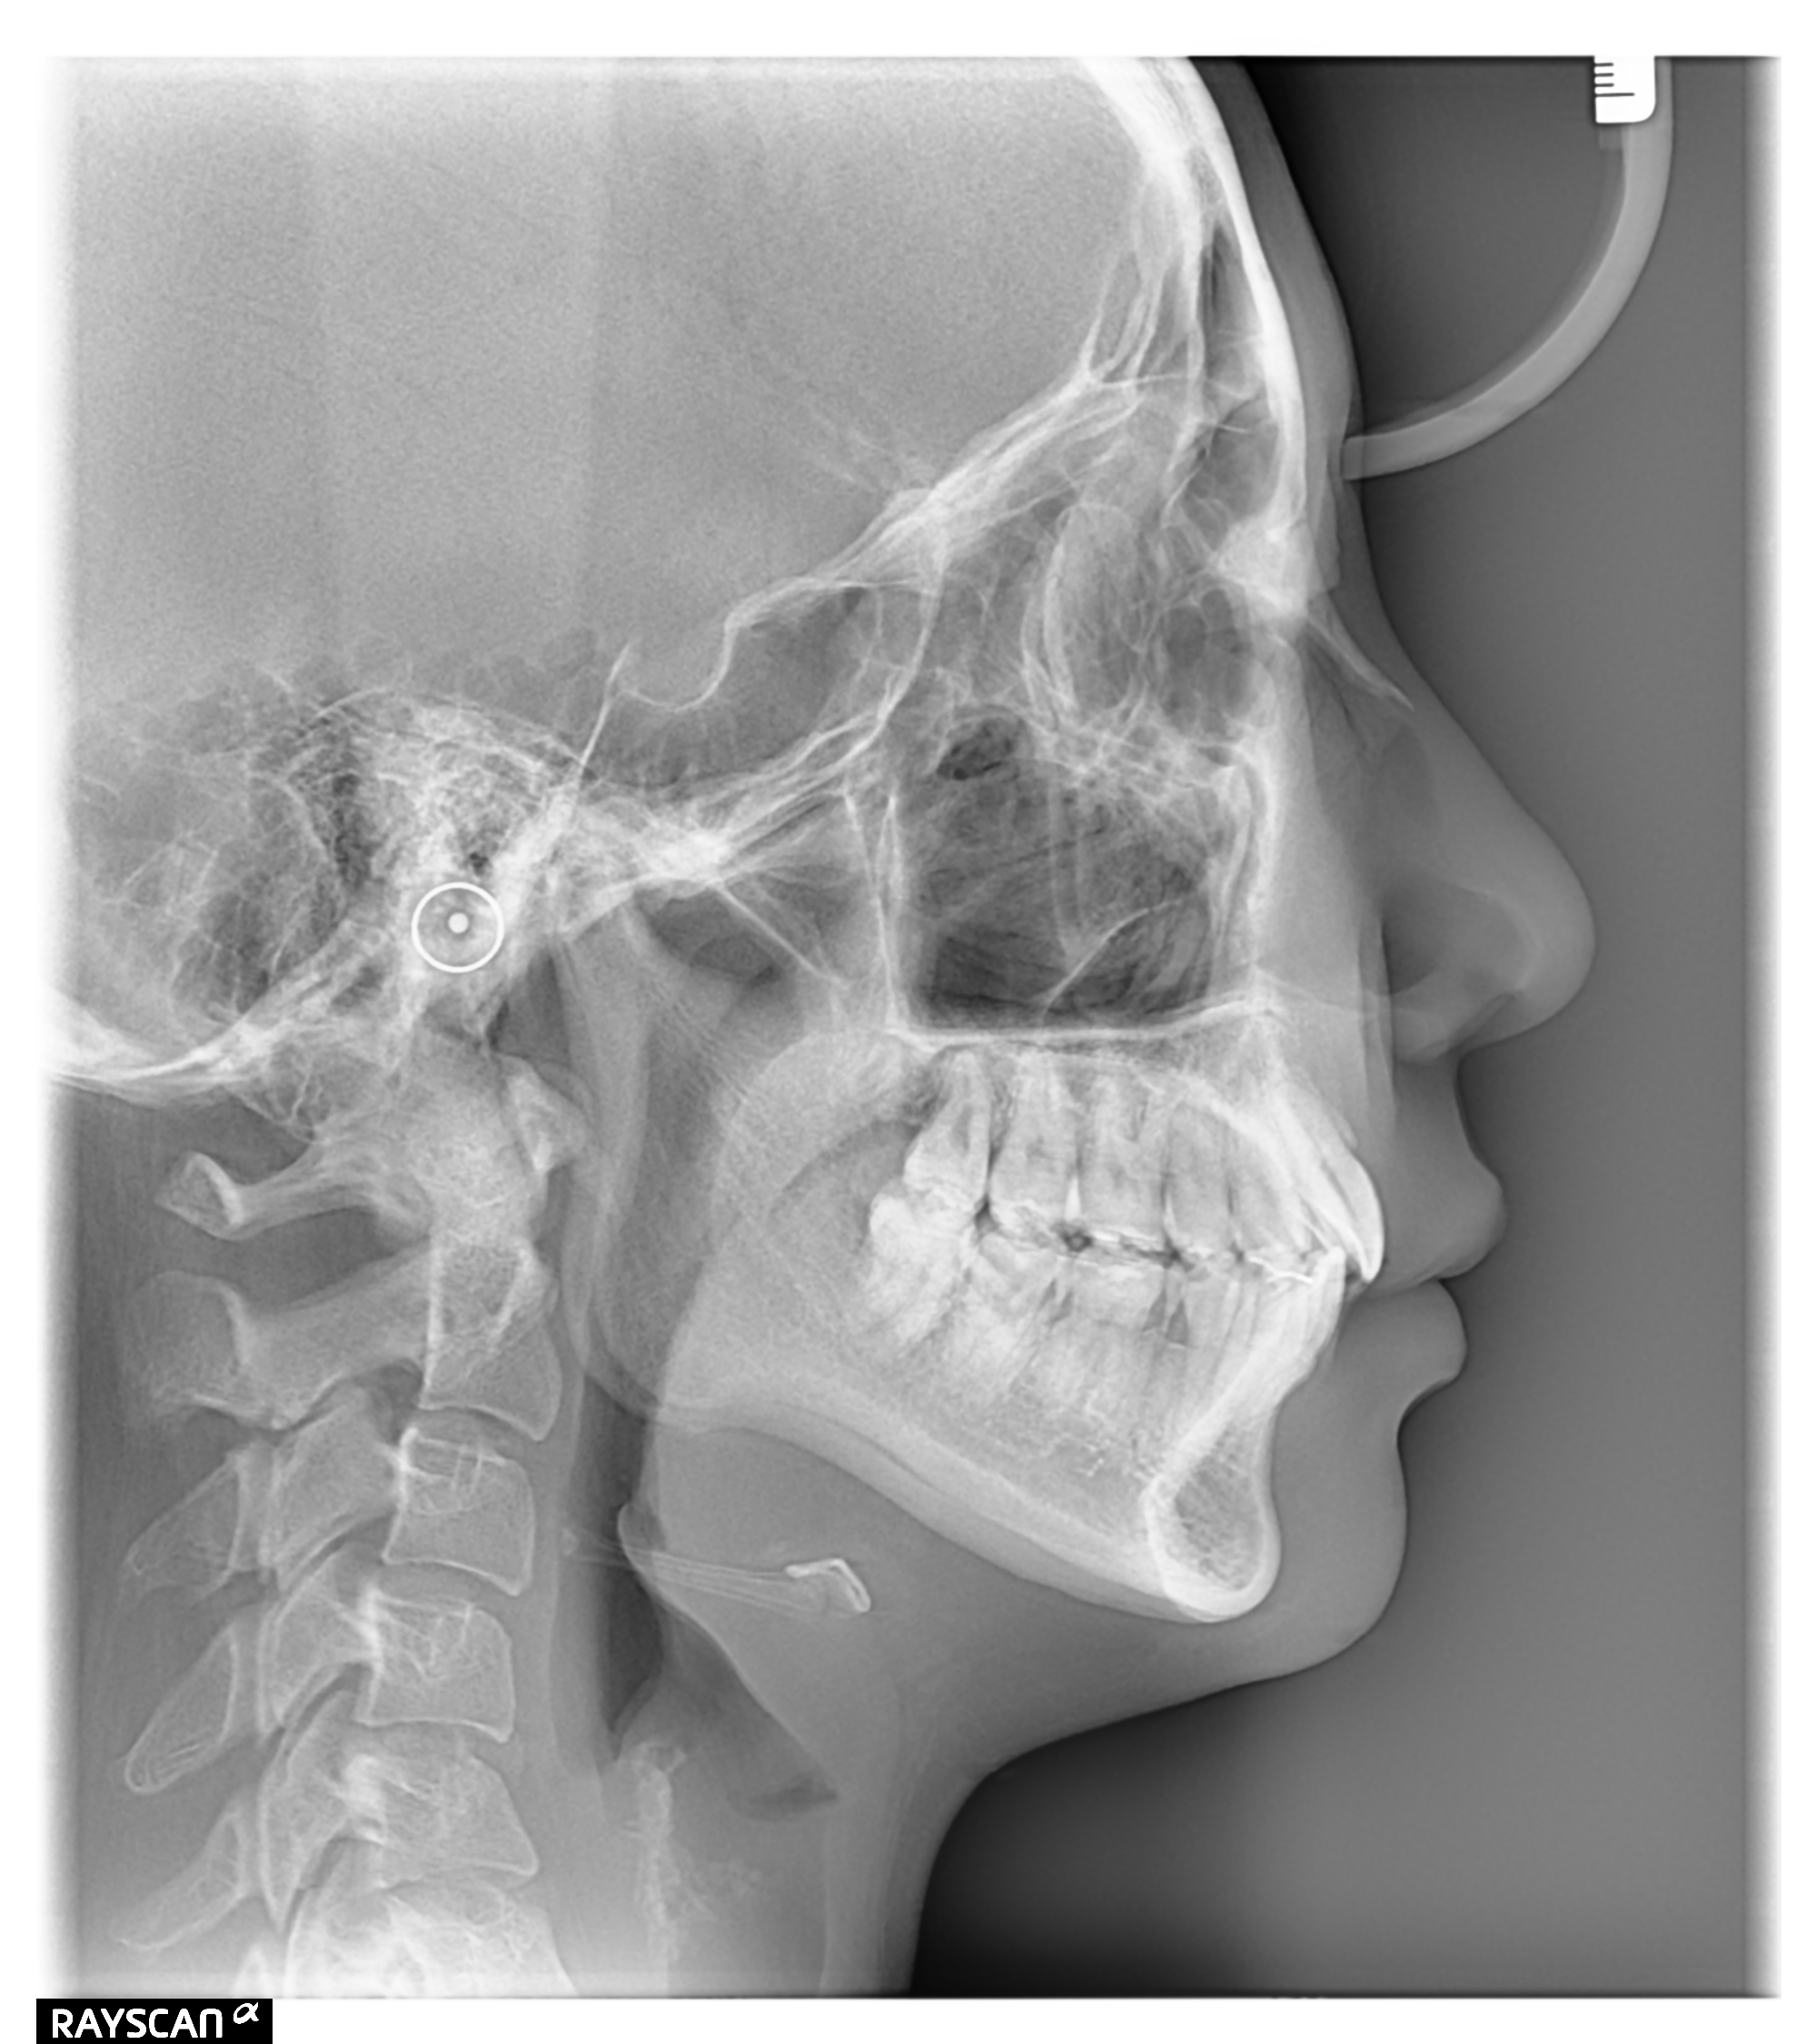

治療前後の側貌レントゲン写真の変化

| 患者様 | 女性 19歳 |

| 診断 | 叢生歯列を伴う上顎前突不正咬合 |

| 治療方針 | 上顎左右第一小臼歯、下顎左右第二小臼歯の抜歯 |

| 治療に使用した装置 | セルフライゲーションブラケット インプラントアンカースクリュー×2 |

| 治療期間 | 2年6カ月 |